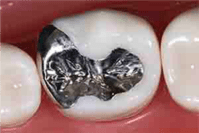

虫歯が大きい場合は、プラスティックを詰めても割れてしまいます。そのため、型採りを行い、銀歯もしくはセラミックのつめ物を作製してセットします。また、虫歯が歯の神経に近い場合、しみたり噛んで痛みが出ますので、覆装と言ってセメントで覆ってあげる治療を行います。

C2で保険適用の金属(銀歯)をセットする治療は、1本約3,500円です。

C2大きい奥歯虫歯治療のつめ物

シルバーインレー セラミックインレー ジルコニアセラミックインレー

特徴 金属ですので、

強度がありますが、

アレルギーという問題と

目立つという問題があります。